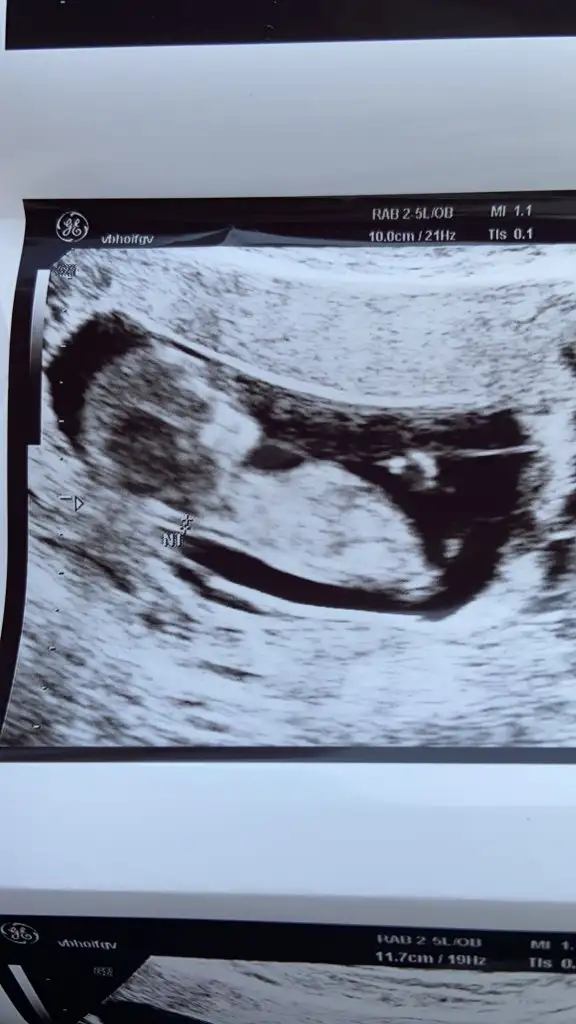

Kızlar 17 haftalık gebeyım Dr ilk erkek dedi 11+6günluk ıken şimdi kız dedı resim paylaşıyorum 11+6gunlukken

Benım gıbı olan var mı